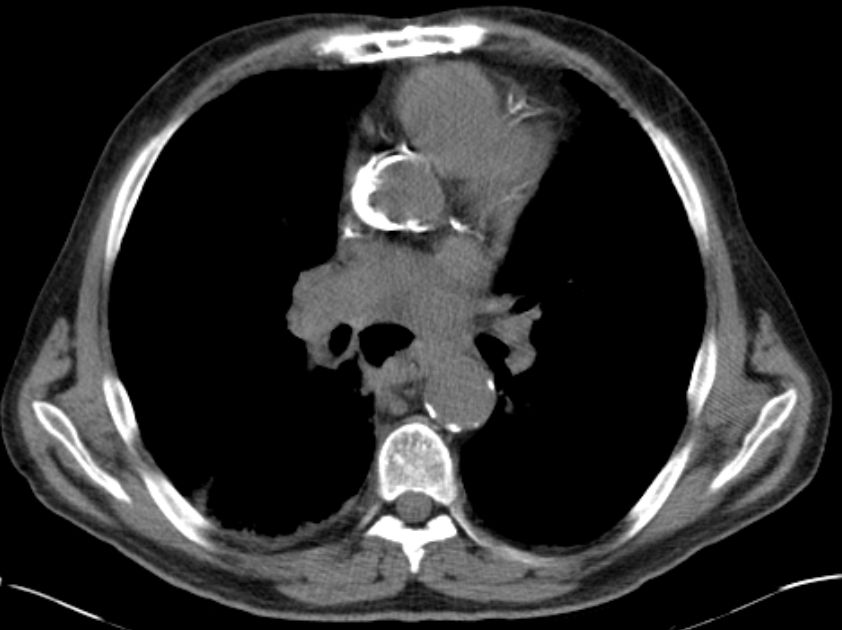

Primär zerebral metastasiertes Adenokarzinom des rechten Unterlappens. Im CT Tumor kavernenartig zerfallend. Jetzt: Sero-Pneu.

Sero-Pneu im CT